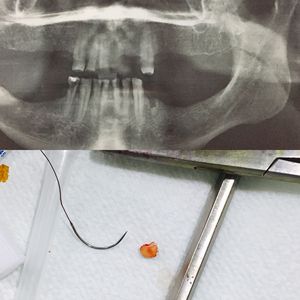

removal of the root left in the apexππ

Radiology

Extraction

Radix